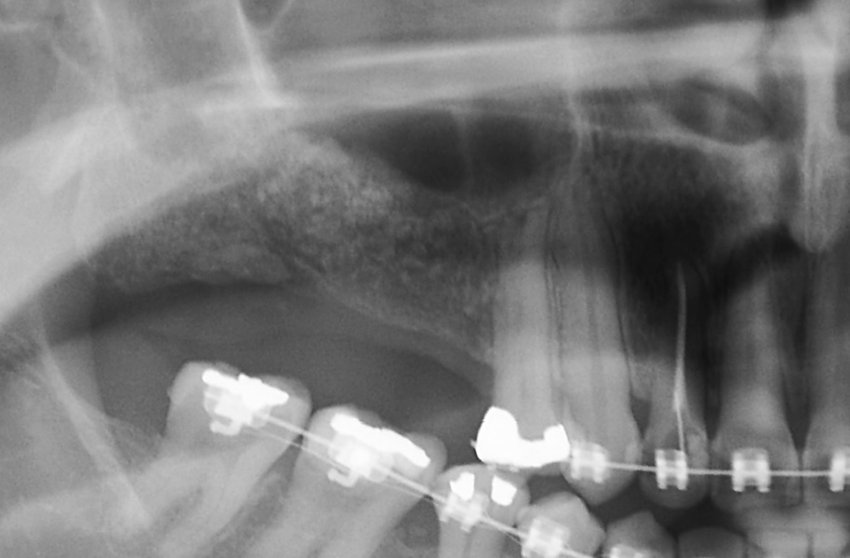

Enxerto de seio maxilar